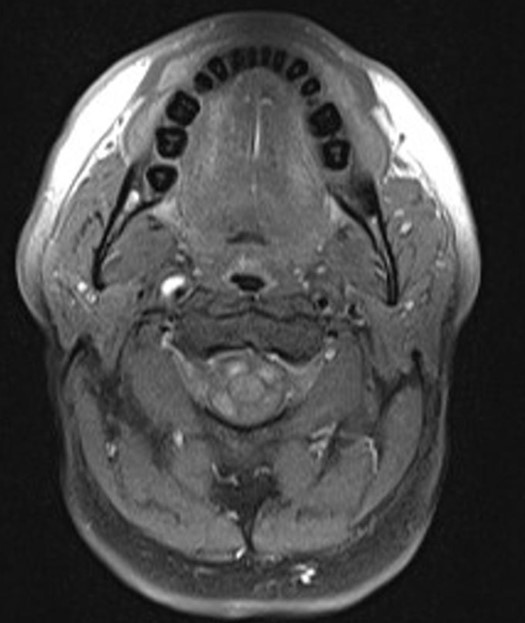

Затемнение на мрт

Затемнение на мрт 140 фото